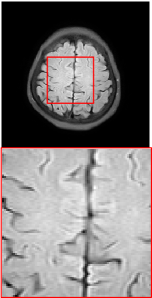

Figure 5 provides the qualitative comparison of the various methods on the four datasets at a scale of 4. The top, second, third, and bottom rows are the SR results under the FastMRI, clinical brain, clinical tumor and clinical pelvic datasets, respectively. The red boxes indicate the zoom-in region of complicated anatomical structures along with their corresponding error maps. Note that the brighter textures in the error maps, the lower the quality of the reconstructed images. As can be seen, compared to methods based on Transformers and CNNs, diffusion-based methods like DisC-Diff and DiffMSR (Ours) are capable of reconstructing high-realistic images with promising reconstruction metric scores (PSNR and SSIM). Nevertheless, while DisC-Diff can reconstruct high-precision MR images, it does not preserve the structure present in the original HR images, introducing some additional information that can affect medical diagnosis. In contrast, our method combines DM and PLWformer, which can preserve the original image’s structure while restoring high-frequency information.

In this section, we present more visual qualitative comparisons. Figures 8, 9, 10, and 11 show the reconstruction results of each method in FastMRI, clinical brain, clinical tumor, and clinical pelvic, respectively. As can be seen, although DisC-Diff can reconstruct MR images with high-frequency information, it fails to preserve the structure and content of the original Target HR image effectively, resulting in image distortion. In contrast, our proposed DiffMSR can restore high-frequency information while preserving the structure of the original HR image, indicating the effectiveness of the joint use of DM and PLWformer.